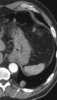

Metastasis from leiomyosarcoma

Leiomyosarcoma, is a malignant (cancerous) smooth muscle tumor. A benign tumor originating from the same tissue is termed leiomyoma. [Source: Wikipedia ]